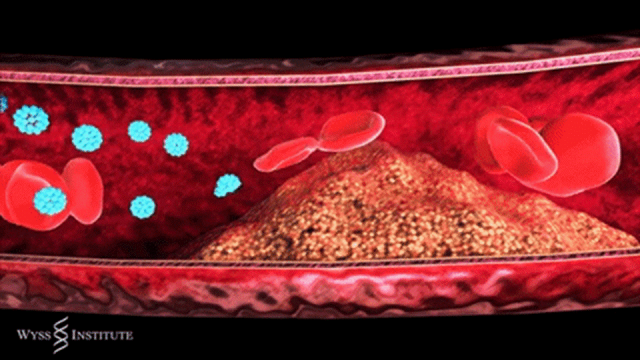

简单来说,动脉粥样硬化是血管壁的一场 “慢性病变”:血液中的脂质在血管壁沉积,伴随炎症反应不断发展,逐渐形成斑块。这些斑块会像 “水垢” 一样堵塞血管,让血流变慢,严重时甚至完全阻断血流,引发致命问题。

近年来,越来越多研究证实,干细胞对于修复血管内皮,促进血管新生,以及通过调控炎症对动脉粥样硬化产生的作用。

切片显示移植干细胞参与修复血管,向内皮细胞分化

间充质干细胞可以分化为内皮细胞,加速受损内皮修复,抑制动脉狭窄的形成。另外,体外输注的间充质干细胞能够向受损部位募集,并进一步分化为内皮细胞,修复损伤血管。